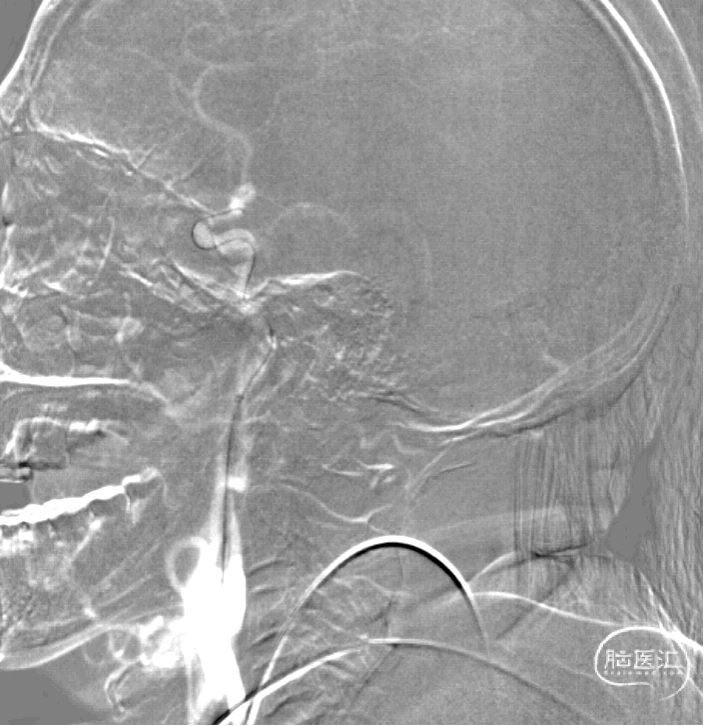

术前造影提示:右侧大脑中动脉M1段起始处闭塞,为责任血管;右侧大脑前动脉经软脑膜支部分代偿右侧大脑中动脉供血;右侧颈内动脉C1起始段中度狭窄。

泥鳅导丝携5F多功能导管和6F长鞘至右侧颈总动脉末端分叉处。在Roadmap下,用0.014"200cm微导丝携0.021"微导管通过同轴技术将通桥银蛇中间导管送至右侧颈内动脉C4段。将微导丝、微导管通过右侧大脑中动脉M1起始闭塞段,微导丝、微导管送至右侧大脑中动脉M2下干远端,退出微导管至支撑导管内,手推造影行微导管首过效应,首过效应阴性,考虑栓塞。通过微导丝将微导管送至右侧大脑中动脉M2下干中段,撤出微导丝。通过微导管将一枚取栓支架(通桥蛟龙6-30mm)送至右侧大脑中动脉M2起始段并释放支架。通过支架铆钉作用将银蛇颅内支撑导管进一步送至右侧大脑中动脉M1起始段,支撑导管接负压持续抽吸,5分钟后向近心端回拉支架,在负压下支架合并颅内支撑导管一起撤出体外。通过长鞘造影显示右侧大脑中动脉血流通畅。

通过同轴技术,通桥银蛇中间导管轻松送至右侧颈内动脉C4段。

微导管首过效应阴性。

将取栓支架(通桥蛟龙6-30mm)释放于右侧大脑中动脉M1分叉远端;通过支架铆钉作用将银蛇颅内支撑导管送至右侧大脑中动脉M1起始段。

运用抽拉结合技术支架联合中间导管抽拉取栓1次,血管再通,mTICI3级。

术后造影显示:右侧大脑中动脉血流通畅。